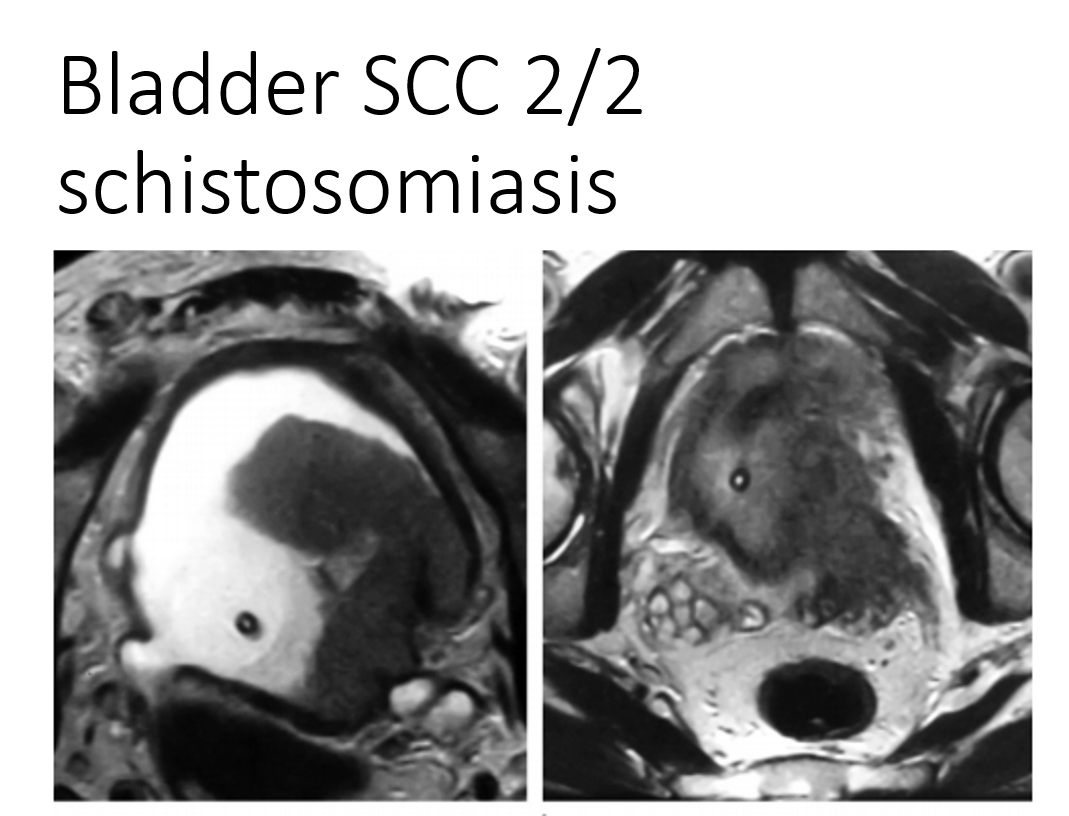

history of schistosomiasis

schistosomiasis